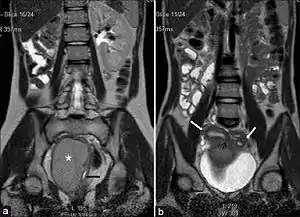

| (a) Coronal Single shot T2W image shows absence of the right kidney. The distended hemivagina (asterisk) is seen on the right side and the normal collapsed left hemivagina with minimal fluid is seen adjacent to it (black arrow). The distended hemivagina ends above the introitus and its contents are hypointense to fat. (b) Coronal Single shot T2W image shows right and left uterine horns (white arrows). The right uterine horn cavity is seen to communicate with the upper end of the fluid collection in right hemivagina (small black arrow) |